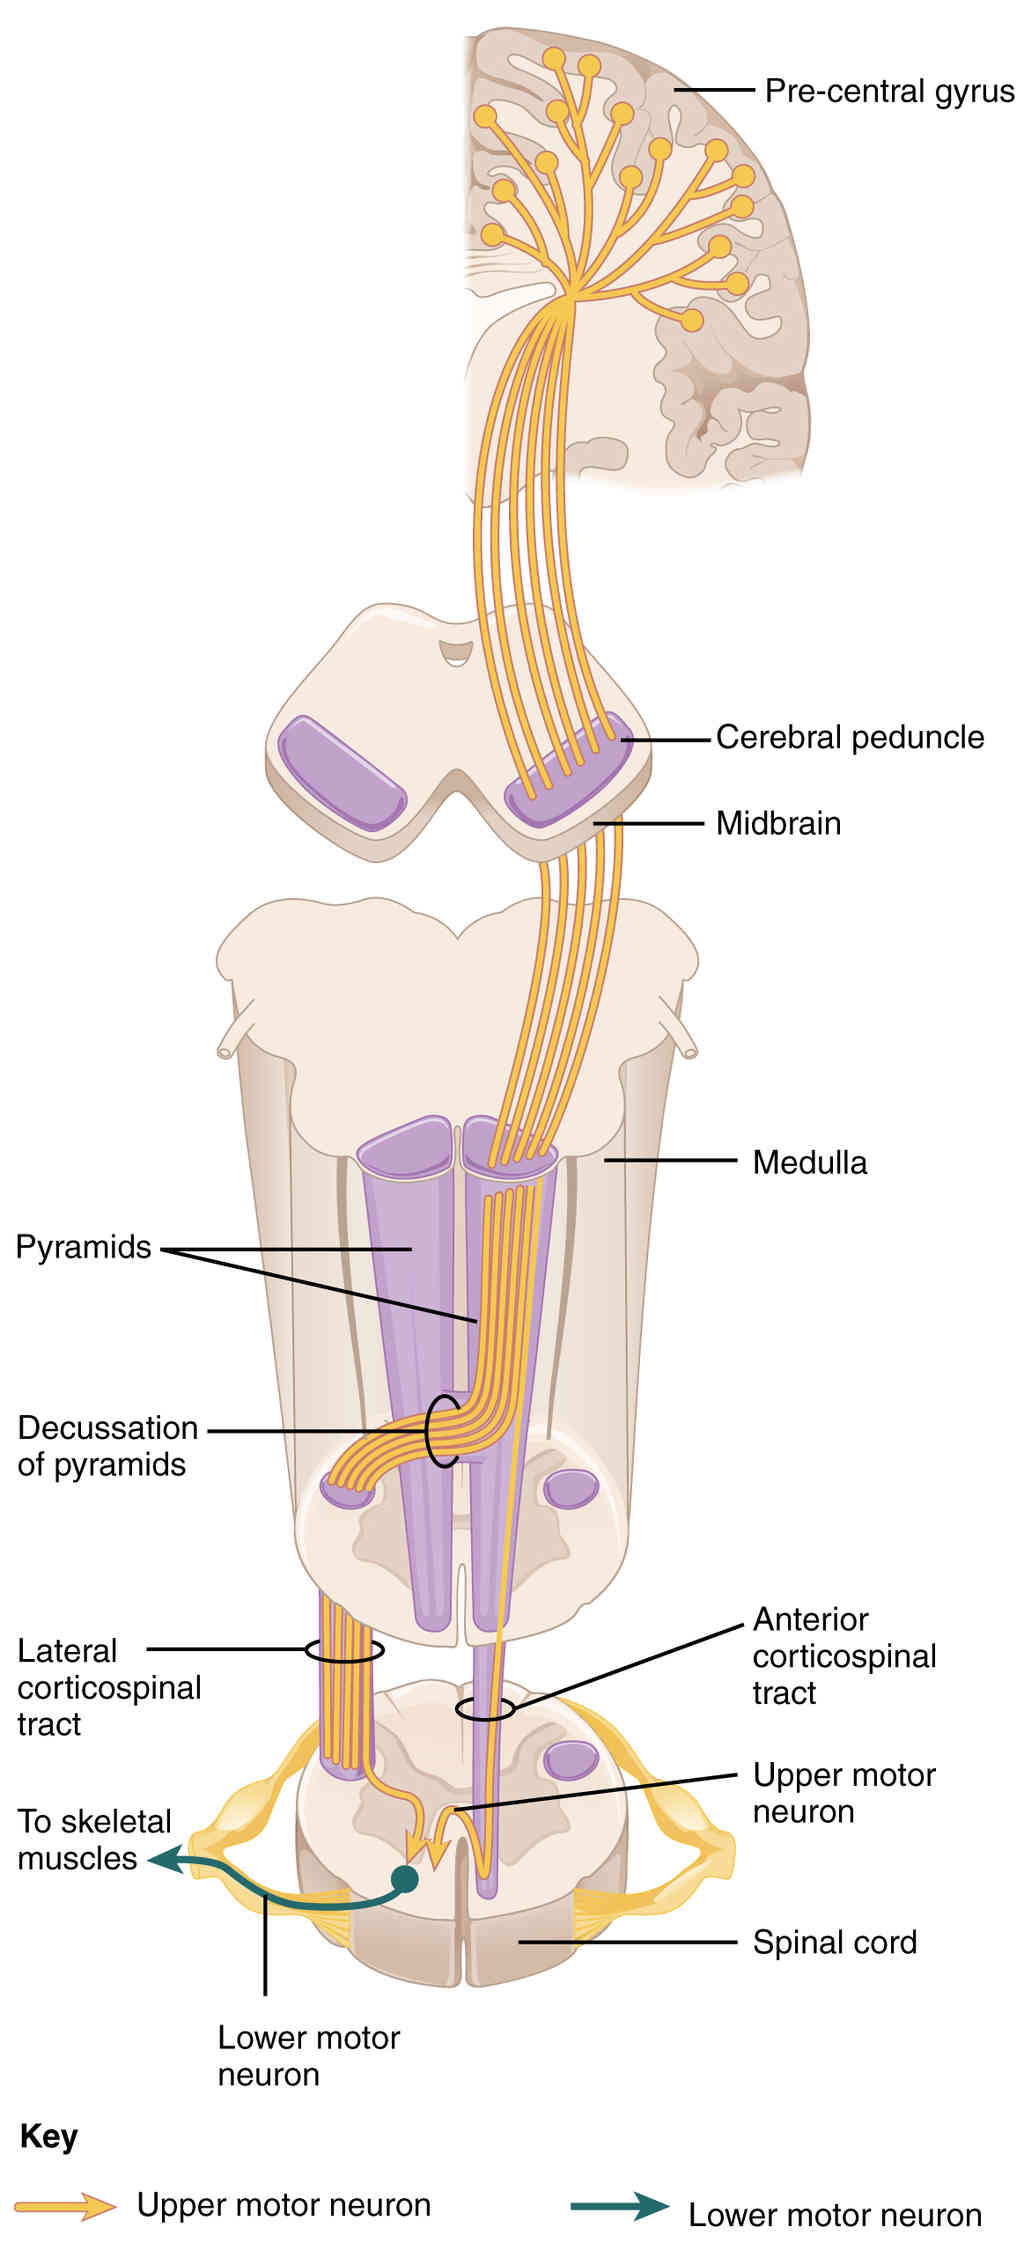

This page is under construction. For now, it is just a resource of the images found in the OpenStax Anatomy and Physiology Handbook. It wil slowly change into a revision tool. Each slide has a number. Use this to refer to the slide. When completed, it will have an unlabelled section, with labelled slides in parallel. On the unlabelled slides, write your answer and use the labelled slide to assess yourself. Keep track by also noting the number on each slide. Improvement at each attempt is important, more so than full marks on a first attempt.